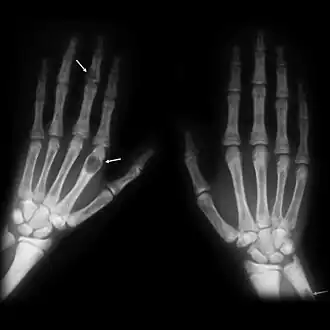

- X-ray of the hands showing brown tumors in the long bones of the fingers

Generally, the first bones to be affected are the fingers, facial bones, ribs, and pelvis.[22][23] Long bones, which are longer than they are wide, are also among the first affected.[23] As the disease progresses, any bone may be affected.[18]

X-rays may also be used to diagnose the disease. Usually, these X-rays will show extremely thin bones, which are often bowed or fractured. However, such symptoms are also associated with other bone diseases, such as osteopenia or osteoporosis.[29] Generally, the first bones to show symptoms via X-ray are the fingers.[22] Furthermore, brown tumors, especially when manifested on facial bones, can be misdiagnosed as cancerous.[29] Radiographs distinctly show bone resorption and X-rays of the skull may depict an image often described as "ground glass" or "salt and pepper".[30][31] Dental X-rays may also be abnormal.[2]